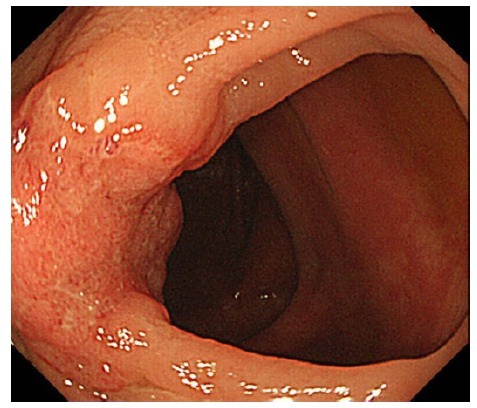

第一次肠镜检查 3 周后行第二次结肠镜检查。肿瘤病灶直径 20 mm,较之前明显缩小(图 2)。标本活检仍显示中分化腺癌(图 3)

图 2 第二次肠镜发现肿瘤直径 20mm,较之前减小,肿瘤溃疡变浅。